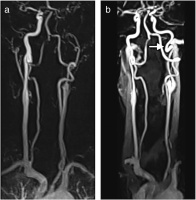

Abbildung 2: (a) Kontrastmittelgestützte MR-Angiographie einer 37jährigen Patientin mit Dissektion und Verschluß der linken A. carotis interna (ACI) unter jahrelanger Therapie mit D-Penizillamin bei Morbus Wilson. Die Verlaufskontrolle nach einem Jahr (b) zeigt die Rekanalisation des Gefäßes und zusätzlich eine Schleife (Coiling) im Bereich der Schädelbasis (Pfeil).